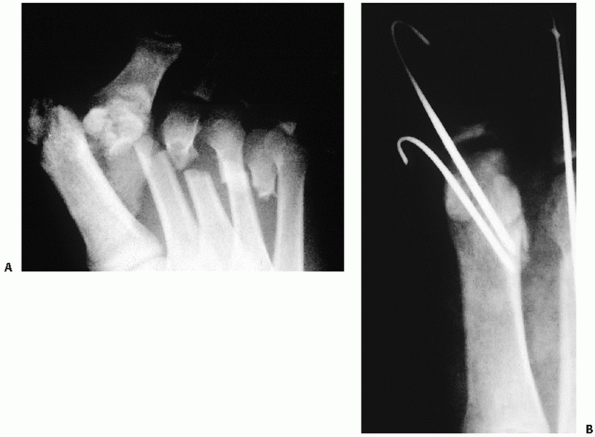

![]() |

FIGURE 60-20 Fracture of the os peroneum. A. Lateral radiograph of acute os peroneum fracture while running. B,C. Three-month follow-up with proximal migration of peroneal fragment up the peroneal tunnel. D. Lateral radiograph of foot after excision of fragments and side-to-side anastomosis of peroneus longus to brevis.